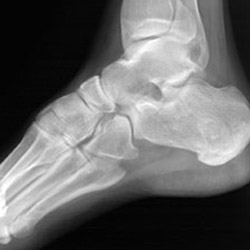

Lateral views of calcaneal fractures

Lateral view